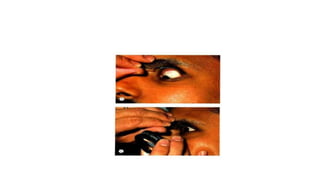

• Examiner should initially stand to the side of the patient, leaning over the patient

• Keep handheld lens approximately 2 inches away from patient's eye, moving it closer or farther away

to focus and refine the view